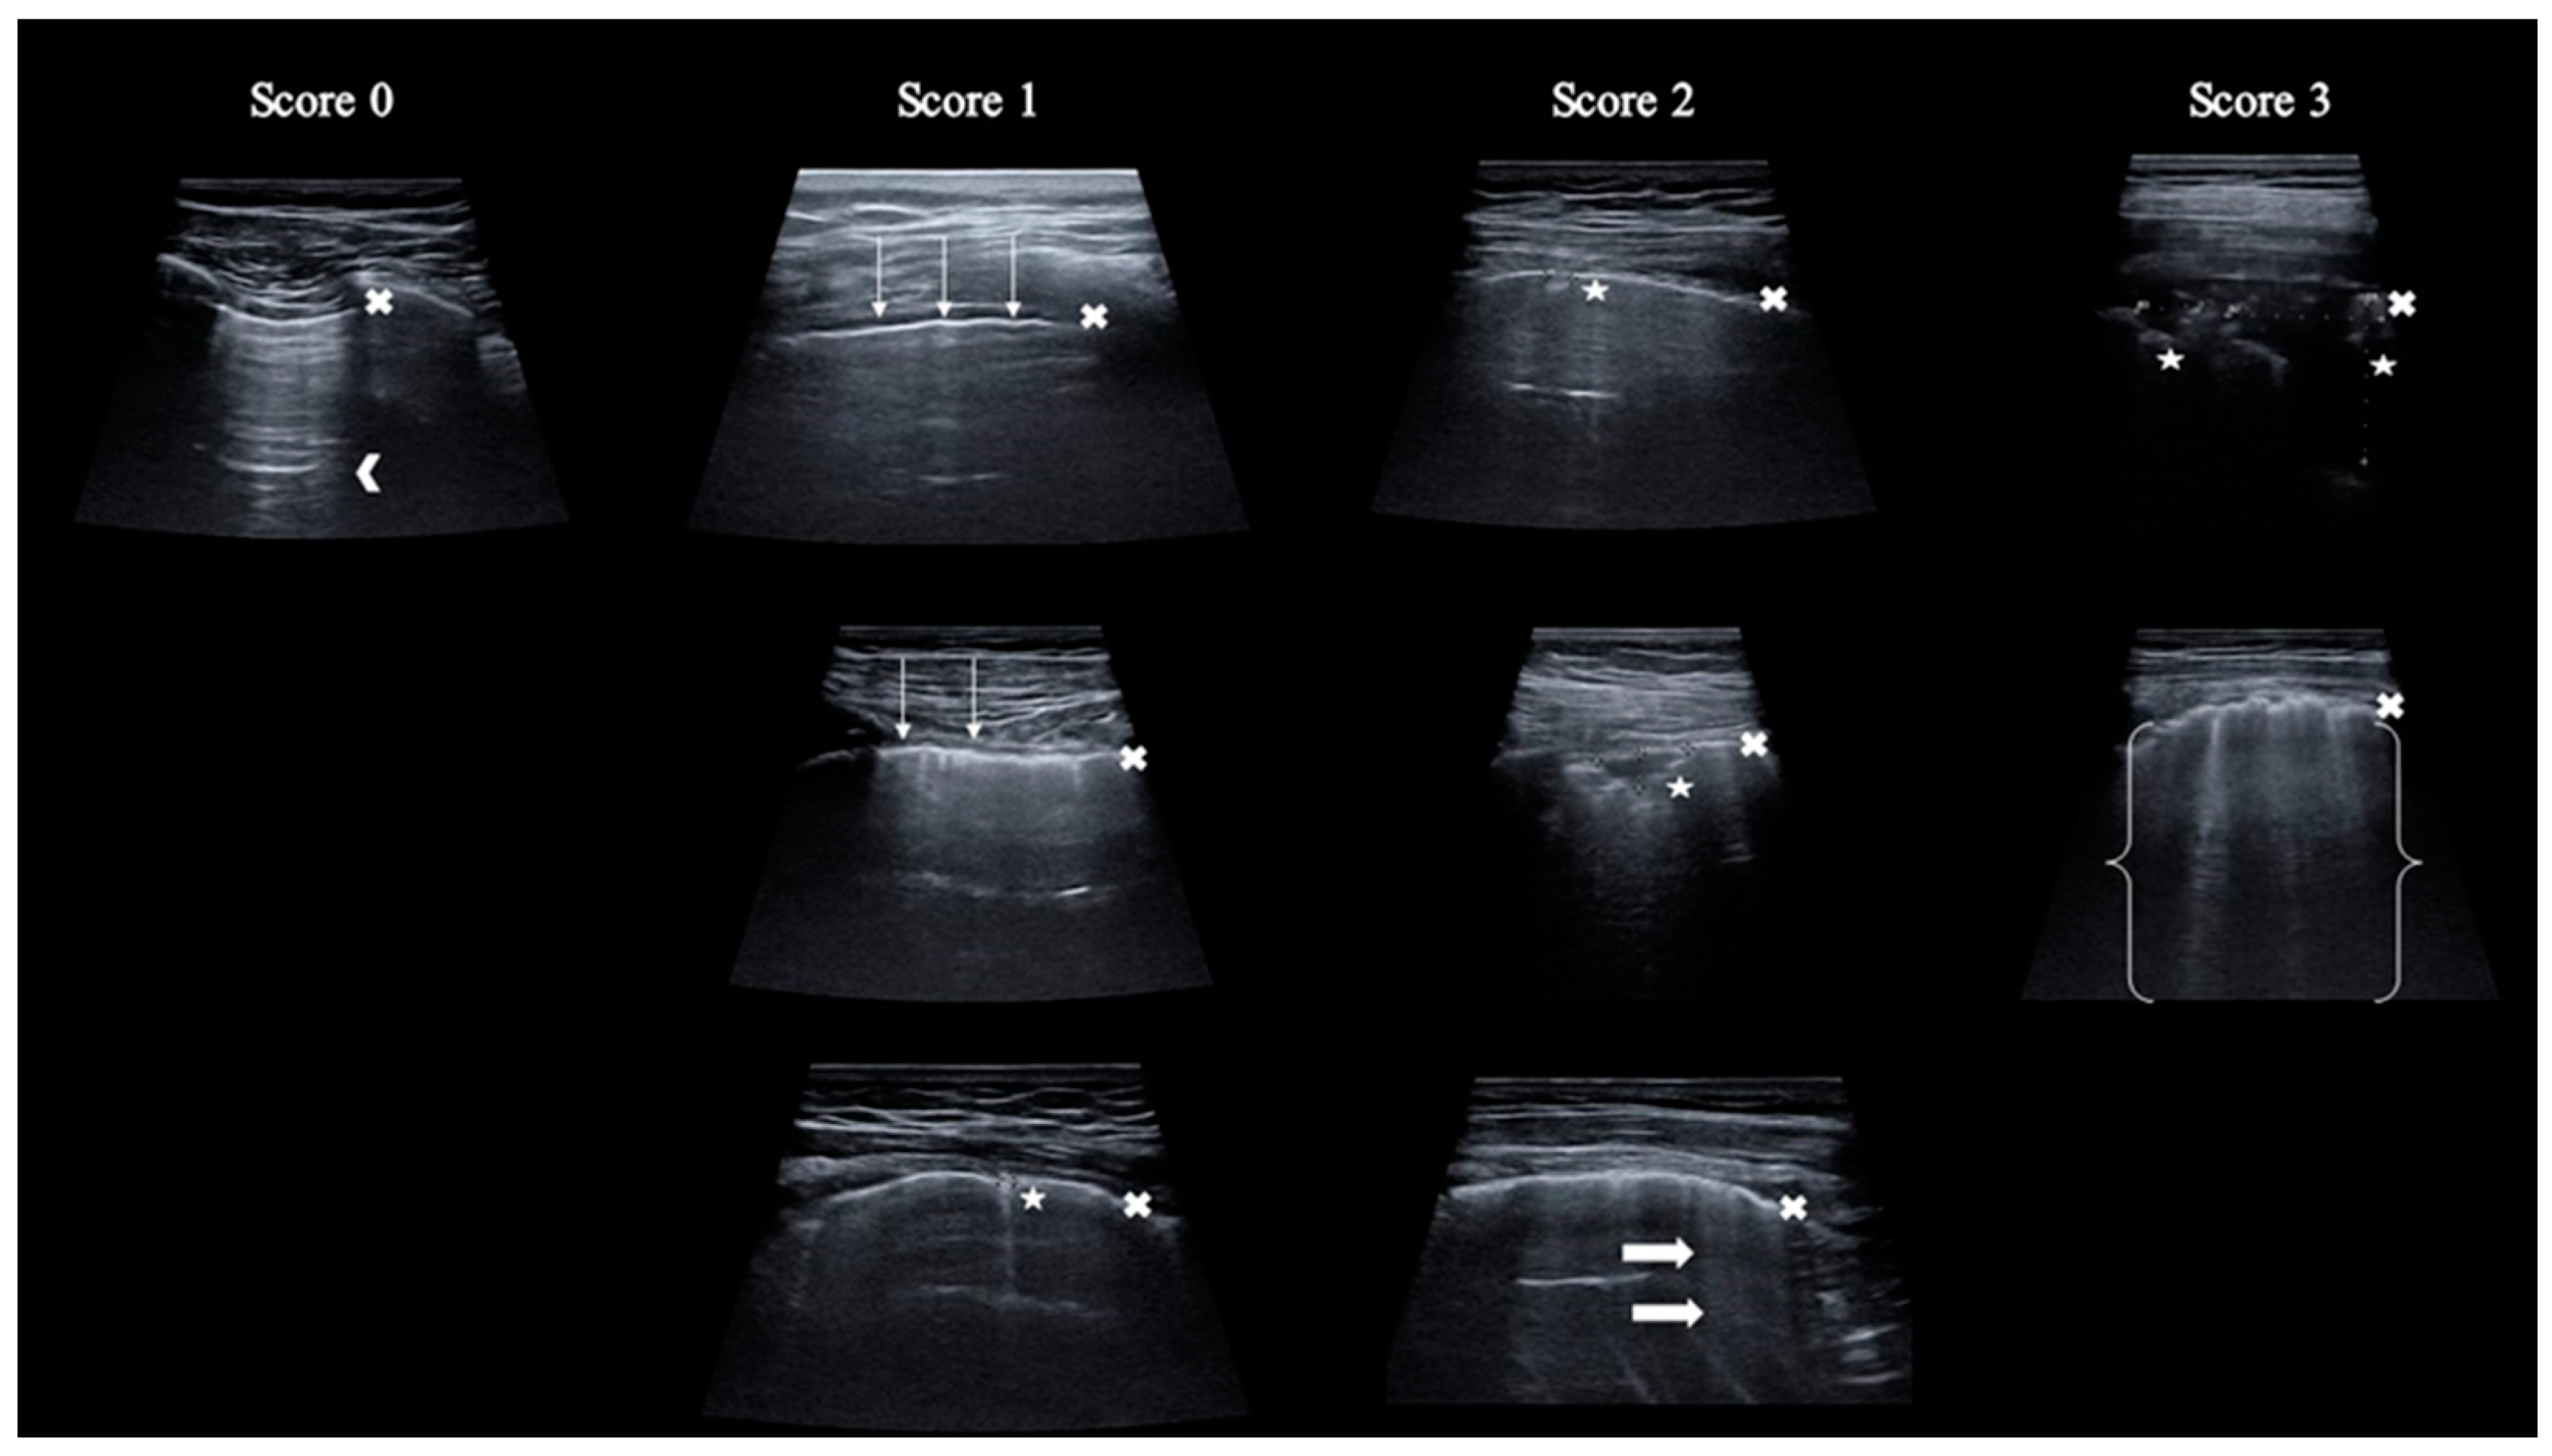

In a specified region, each intercostal space underwent assessment for normal signs and pathological artifacts. Each area was scored, ranging from 0 to 3 points, depending on the pathological lesion described (Table 1 and Figure 2). The total score was calculated by adding up individual scores from each of the 12 regions, with a potential rate of 0 to 36 points. The results of the chest CT scan were blinded to the LUS operator.

Figure 2. Graphical presentation of LUS scoring scale. Legend: x—pleural line; arrowhead—A-line; thin arrow—irregular pleural line; asterisk—consolidations; thick arrow—B-line; bracket—white lung.

ScoreDescription

0Regular and continuous pleural line, presence of A-lines

1Irregular or broken pleural line, or consolidation ≤ 2.5 mm, or ≤3 B-lines

2Consolidation > 2.5 mm ≤10 mm, or >3 B-lines

3Consolidation > 10 mm, or pleural effusion, or coalescence B-lines, or “white lung” image